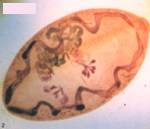

⑴腦脊液痰或糞便檢查可查獲並殖吸 蟲蟲卵

2.痰和腦脊液中可發現蟲卵。皮下結節活檢偶見蟲體。